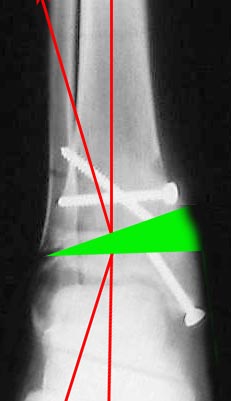

Согласен, тут деформация меньше, но все-таки заметная, почти 20 градусов. Я бы устранял ее как на приложенной картинке.

При таком варианте с аппаратом все легко и просто. С пластиной - должны быть трудности. Может быть, следовало бы планировать коррекцию как-то иначе? Как?

Коллеги , поздравляю всех с наступающим Новым годом и желаю счастья , здоровья , успехов ! Чтоб заживало и срасталось ! Благодарю всех за обсуждение . решил остановиться на аппарате с остеотомией Делать думаю после праздников (срок будет около 4 месяцев). Два вопроса : Что лучше сделать с наружной лодыжкой и при помощи чего Александр Николаевич нарисовал такой симпатичный рисунок ? (TraumaCad ? )

Пока провести спицу через обе кости ниже уровня остеотомии большеберцовой. Если малоберцовая не срастется к моменту снятия аппарата, вернуться к этому вопросу.

> нарисовал такой симпатичный рисунок ? (TraumaCad? )

;-) Фотошоп.